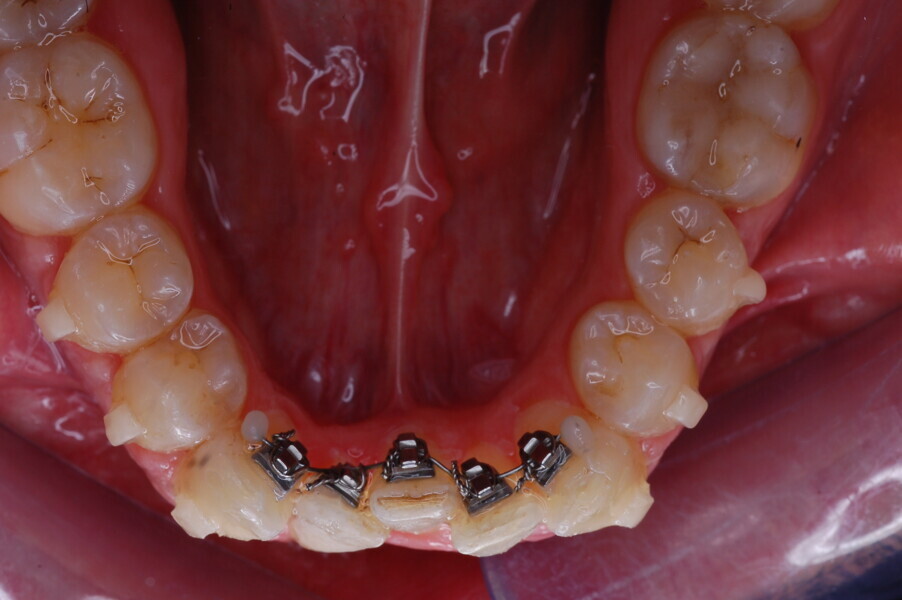

Fig. 37–44: Sequential intra-oral photographs illustrating progressive alignment of the mandibular arch.

Fig. 38.

Fig. 39.

Fig. 40.

Fig. 41.

Fig. 42.

Fig. 43.

Fig. 44.